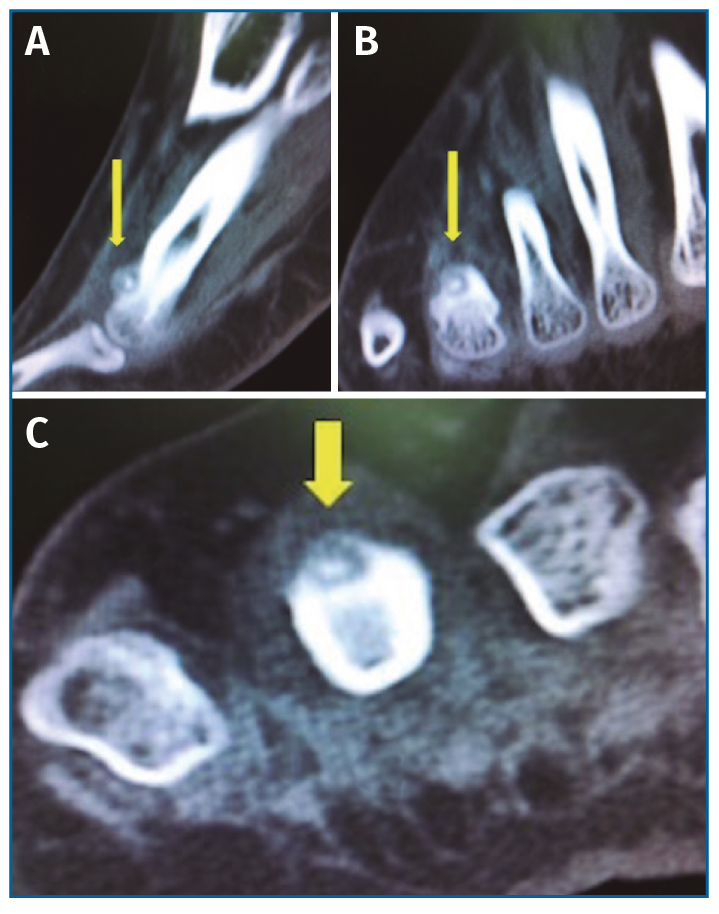

Con el objetivo de determinar las características de la lesión detectada en la RM, se indicó una gammagrafía ósea con tecnecio en 3 fases, que mostró un foco de hipercaptación de morfología redondeada en la cabeza del cuarto metatarsiano, compatible con una fractura de estrés (Figura 4). Una nueva RM en dispositivo convencional de 3T permitió detectar una lesión de 6 mm de diámetro en el dorso del cuello del cuarto metatarsiano, compatible con un osteoma osteoide (OO) (Figura 5). La TC de cortes finos a dicho nivel confirmó definitivamente la lesión tumoral (Figura 6).

Figura 6. Tomografía computarizada. A: corte sagital; B: corte coronal; C: corte axial. Imagen de la lesión radiolúcida, de contorno bien definido con punto central denso en dorso del 4.º metatarsiano, compatible con osteoma osteoide.

Figura 7. Tomografía computarizada durante la radiofrecuencia. Cortes coronales. A: imagen de osteoma osteoide en dorso del 4.º metatarsiano; B: aguja de radiofrecuencia en situación subcutánea y con dirección hacia el osteoma osteoide; C: aguja de radiofrecuencia en el interior del osteoma osteoide.